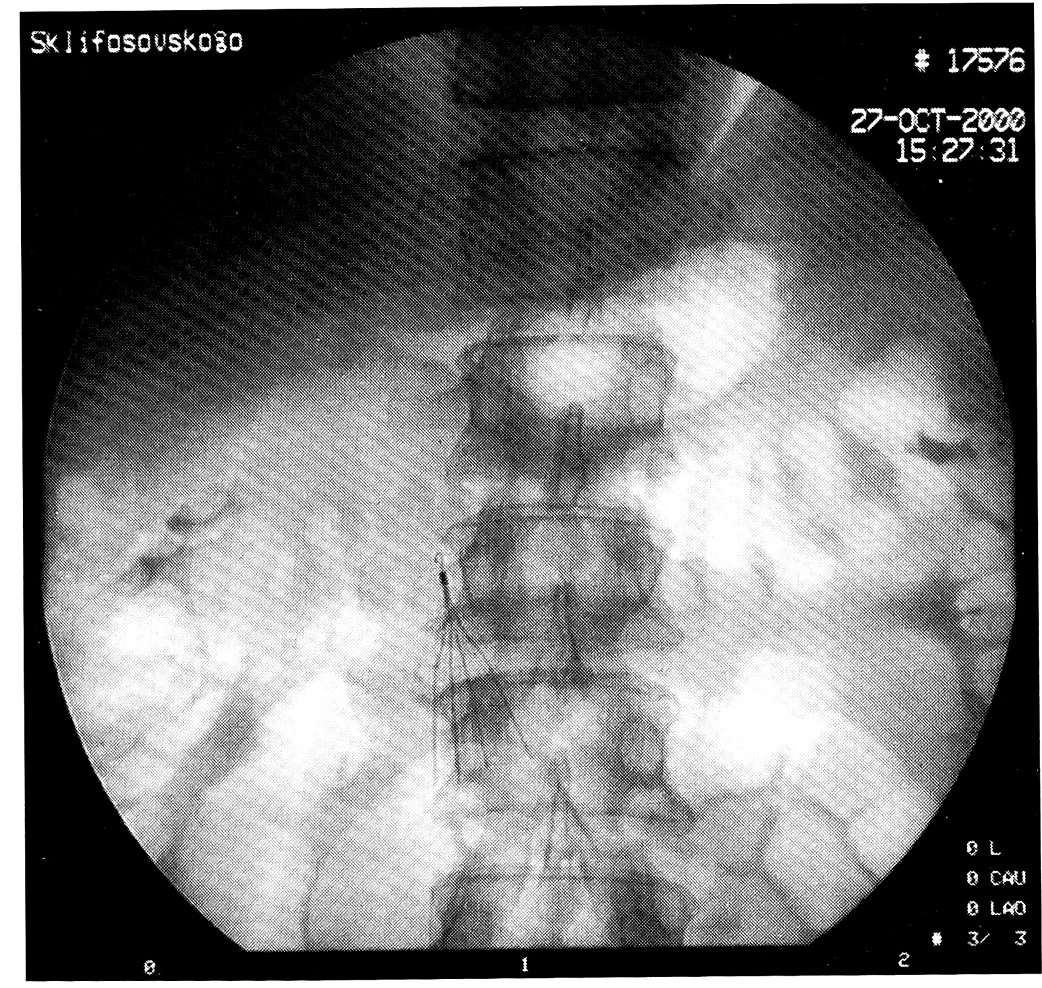

Основным хирургическим методом профилактики тромботических осложнений у больных с политравмой являлась имплантация кава-фильтров. Этот метод считали показанным в следующих случаях: при эмбологенном флеботромбозе в илеокавальном сегменте, при массивной ТЭЛА, рецидивирующей ТЭЛА, в том числе с неустановленным источником эмболизации, при наличии осложнений либо противопоказаний к гепаринотерапии у больных с флеботромбозом или ТЭЛА. Исходя из этого 3 больным с «флотирующими» тромбами и 5 пострадавшими с ТГВ и ТЭЛА была произведена имплантация кава-фильтров — без дальнейших осложнений (рис. 2).

Рис. 2. Рентгенологический контроль положения кавафильтра.